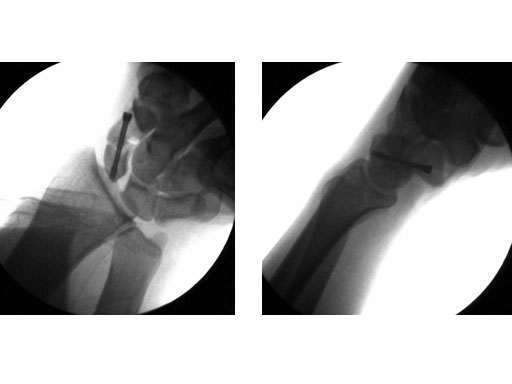

24-year-old male with an acute scaphoid wrist fracture treated by percutaneous fixation with a 3.0 mm headless compression screw under regional anesthesia.

Fig 2ab Intraoperative images.

Fig 3ab Postoperative images.

Case provided by Doug Campbell, West Yorkshire, GB